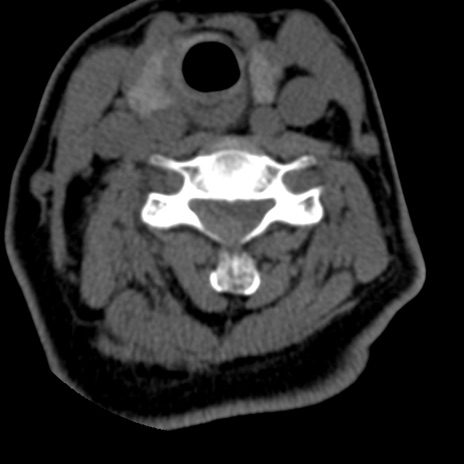

症例50 頚椎CT(横断像)

頚椎CT